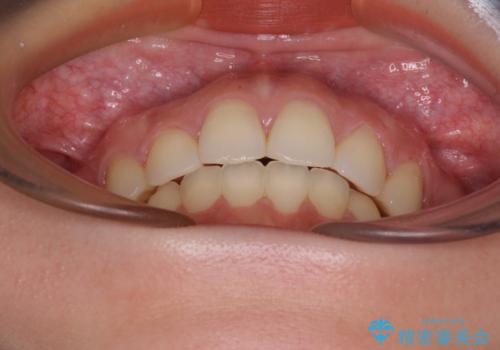

- 口元の突出感を気にして来院された患者様です。

上下左右の第一小臼歯4本を抜歯して口元を下げる治療計画としました。

目立たない装置が希望であったため、上顎が裏側装置である、ハーフリンガル装置を選択されました。